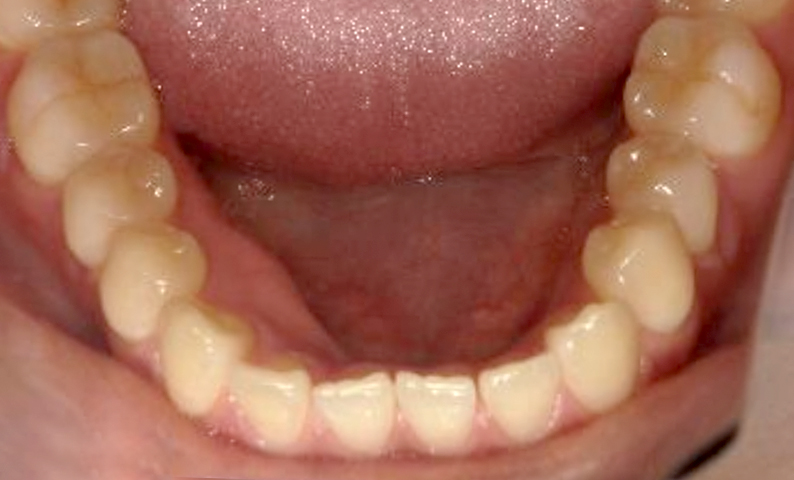

| 治療前 | 治療後 |

|---|---|

|